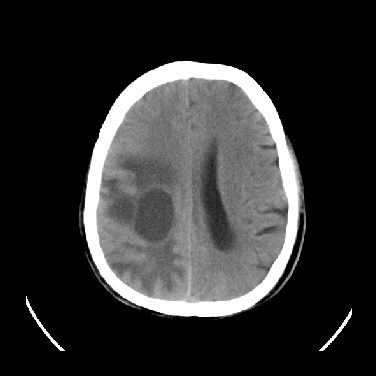

男,45岁,左侧肢体乏力1周。ex:胸片示:两肺团块状、斑片状密度增高影,其内可见小空洞。支纤镜、经皮肺穿示:干酪样物。

考虑右侧顶叶脑脓肿形成。

考虑右侧顶叶脑脓肿形成

右侧顶叶脑脓肿!支持!

考虑右侧顶叶脑脓肿(结核性?)。